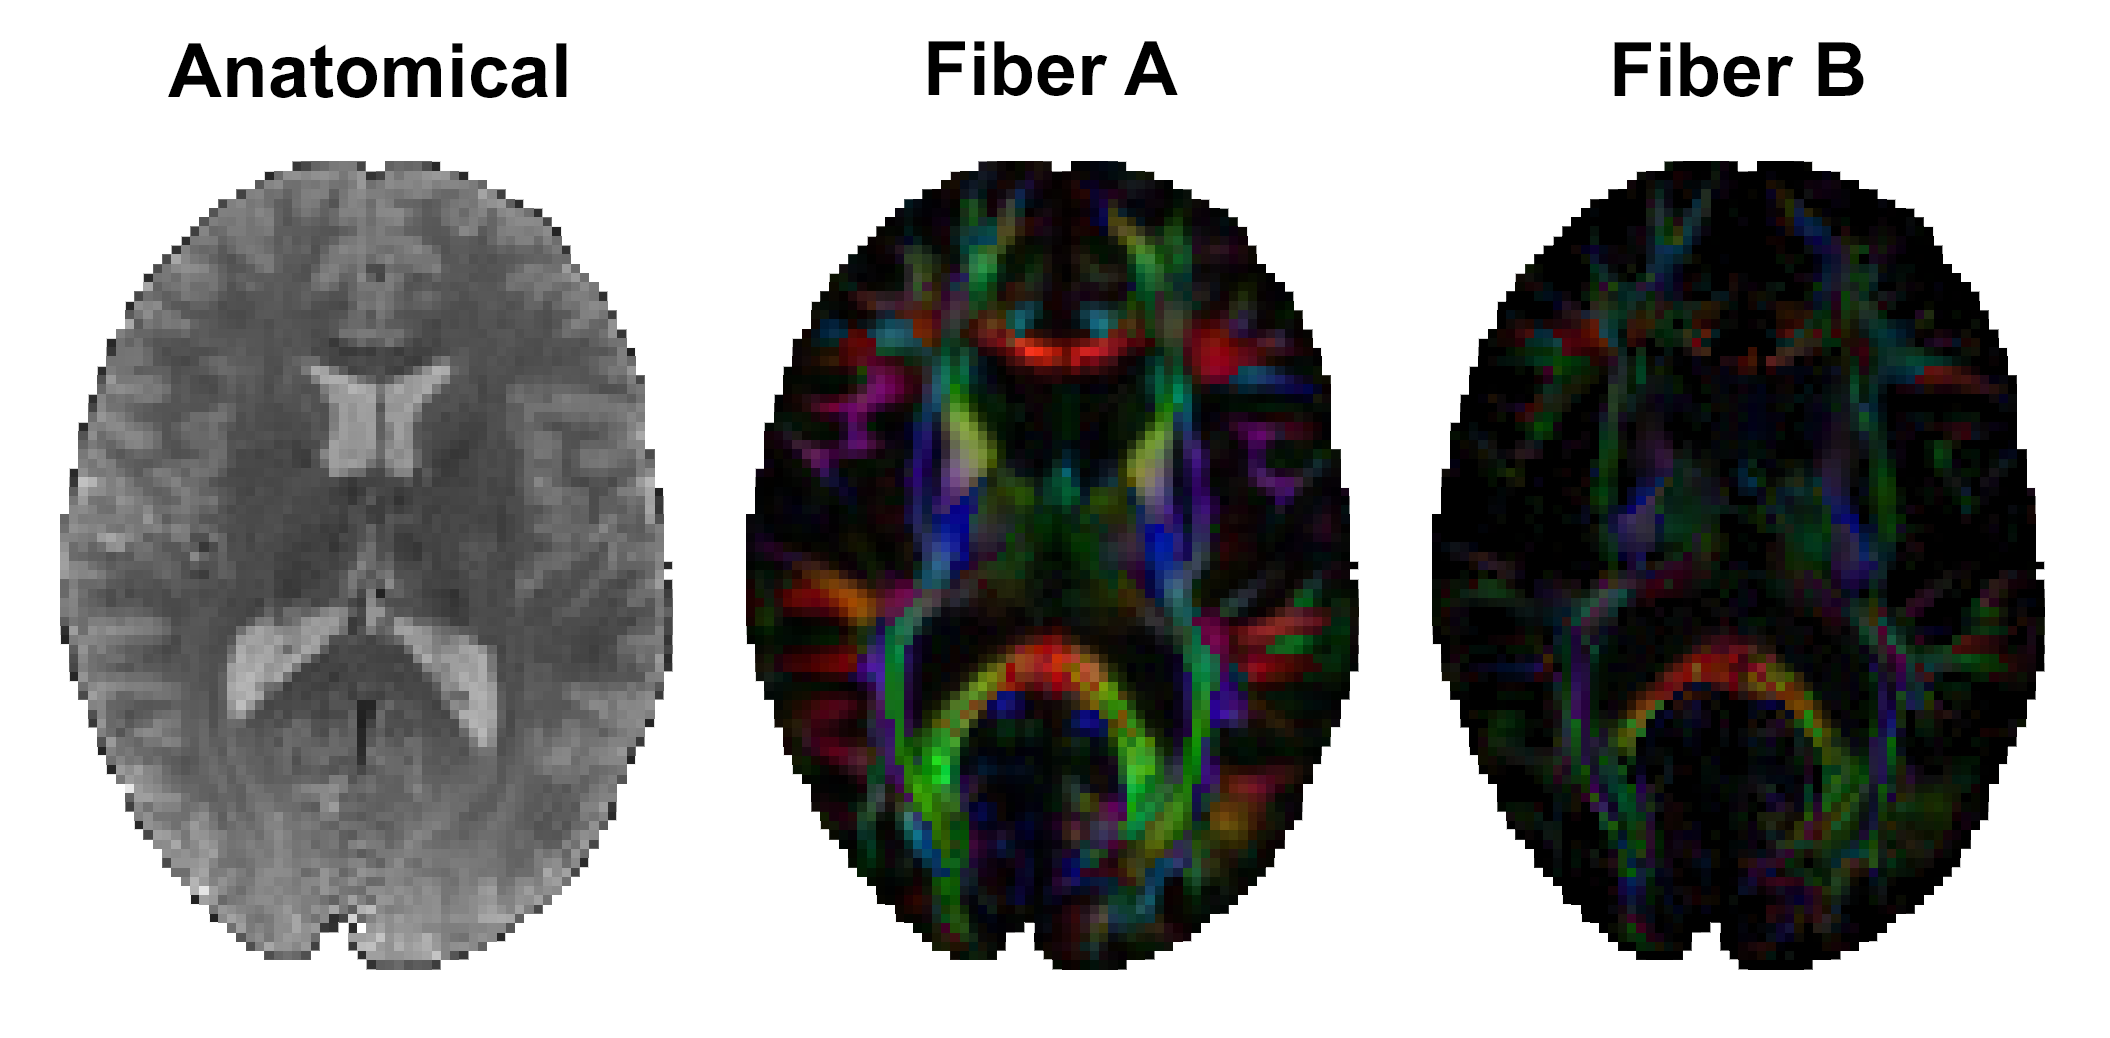

In vivo imaging protocol: MRE and diffusion MRI data was collected and reported in [Smith 2022]4. Multi-excitation MRE acquisition at 2 mm isotropic resolution generated two displacement fields: with anterior-posterior left-right vibrations, both at 50 Hz. Diffusion data at 1.5 mm resolution (128 directions, b = 1500 and 3000 s/mm2) was processed with bedpostx in FSL to estimate up to two axonal fiber directions (Figure 3) in each voxel5,6. Here we show data on a 26 yo female subject.

Figure 3: Two-fiber DTI colorFA maps for the in vivo data. These same fiber direction maps were used to build the finite element simulation model.